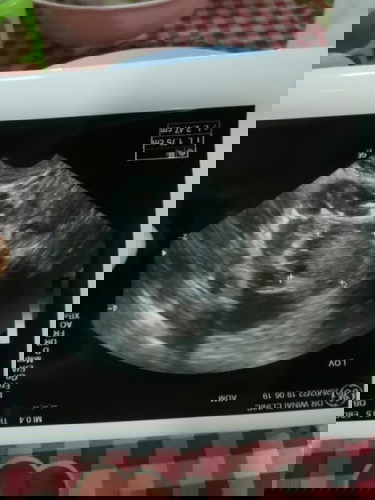

ต้องตั้งครรภ์กี่สัปดาห์คะ ถึงจะซาวด์ทางช่องคลอดแล้วเห็นถุงการตั้งครรภ์ เมื่อวานซาวด์แล้วคุณหมอบอกยังไม่เจออะไร แอบกังวลค่ะ